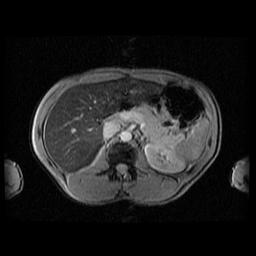

Faible surcharge (chf=50µmol/g, Signa 1,5T)

Copyright - Yves Gandon - Imagerie Médicale -Rennes.